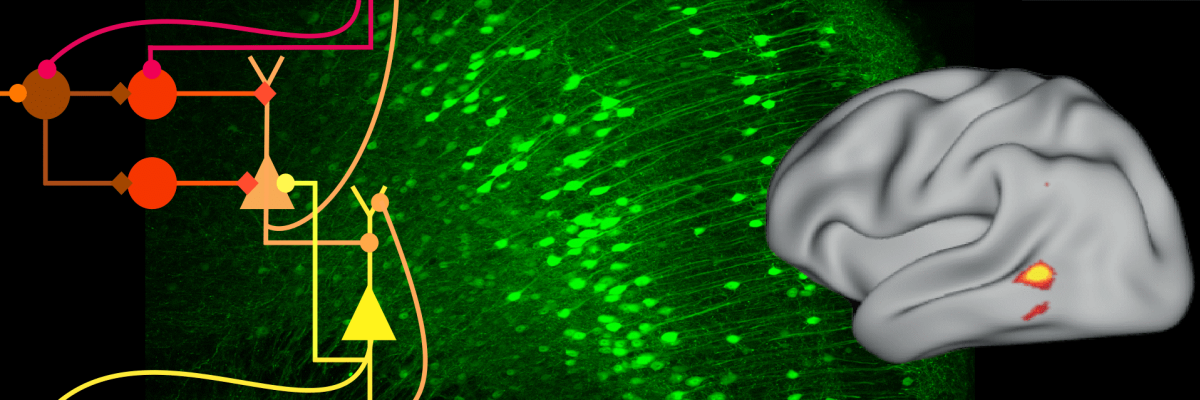

Computational Neuroscience

tight crop of part of an image of a circuit model

Models of brain decision networks

Neural circuits underlying motor function and dysfunction

magill banner

Some of the basal ganglia nuclei with their partner circuits in the thalamus and cerebral cortex.

Neural dynamics and their control in human disorders of movement

motor

Rendered whole brain magnetic resonance image showing which cortical areas have their activities coupled with those in the motor region of the subthalamic nucleus in Parkinson’s disease. Coupling is determined by simultaneous recordings of magnetoencephalographic activity and deep brain recordings in patients with electrodes implanted for deep brain stimulation treatment. Representative deep brain waves are also shown. The effects of drugs and of high frequency stimulation on coupling and deep brain activity can thereby be determined, and provide clues as to how treatments can be improved.